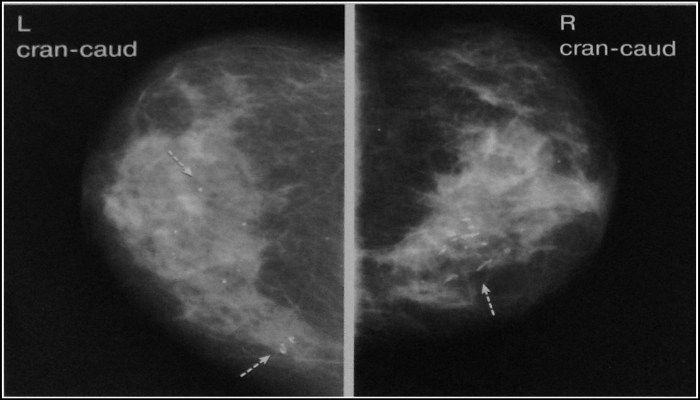

Самым точным методом диагностики является маммография. Это рентгеновское исследование тканей молочной железы, которое позволяет четко визуализировать пораженные участки. Диффузные изменения легко отличить от доброкачественных опухолей и злокачественных новообразований. Аналогичные результаты можно получить и при ультразвуковом исследовании. В большинстве случаев нет необходимости в более дорогих методах диагностики, таких как МРТ, КТ или цифровая маммография.

В процессе диагностики обязательно проводятся мероприятия, направленные на различение доброкачественных и злокачественных поражений. Например, маммографию могут назначить несколько раз в разные дни менструального цикла, чтобы получить более точную информацию о изменениях в опухоли. При наличии ракового процесса опухоль сохраняет свои размеры и форму, тогда как очаговая форма мастопатии молочной железы проявляется изменчивыми кистами, которые могут быть то более заметными, то менее.